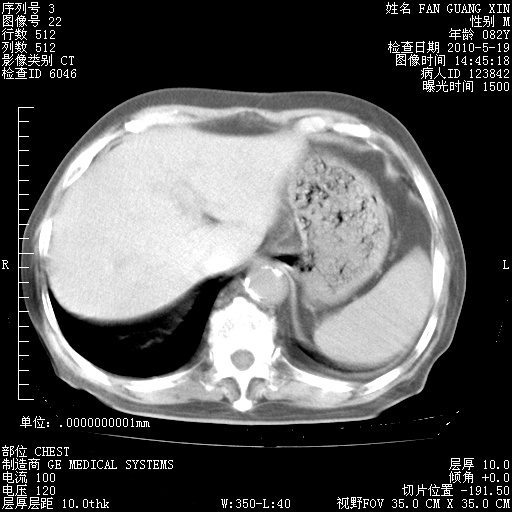

治疗3周后的肺部CT纵隔窗

从胸部影像学来看,的确有好转。至于目前为何发热不甚清楚?除了发热还有其他症状如有无喀痰,痰呈丝状吗?等等。尽量搜寻有无致发热其它可能原因?真菌?其它?如果的确无其他致发热的原因,考虑将甲强龙调至60-80mg bid/日。免疫全套基本无异常,考虑多系特发性肺间质纤维化

阅读此次胸部CT,肺间质渗出性改变较入院时有吸收。目前从体温、白细胞、中性分叶明显增高,肯定存在细菌感染(发生医院感染哦,若无消化道及泌尿系统等感染的依据,肺部感染可能大)。若你院头孢哌酮舒巴坦钠耐药率较高,同意你的方案,若48小时体温仍高,可考虑使用碳青霉稀类抗菌药物,同时可予超声雾化、注意滴数时加大液体量。白蛋白33.30g/L较低哦,需加强营养等支持治疗。